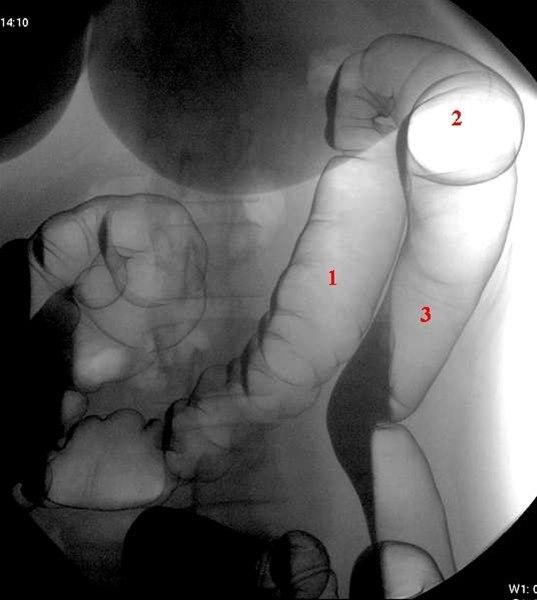

Venstre colonflexur avfotografert med pasient i høyre sideleie

- Colon transversum

- Venstre flexur

- Colon descendens